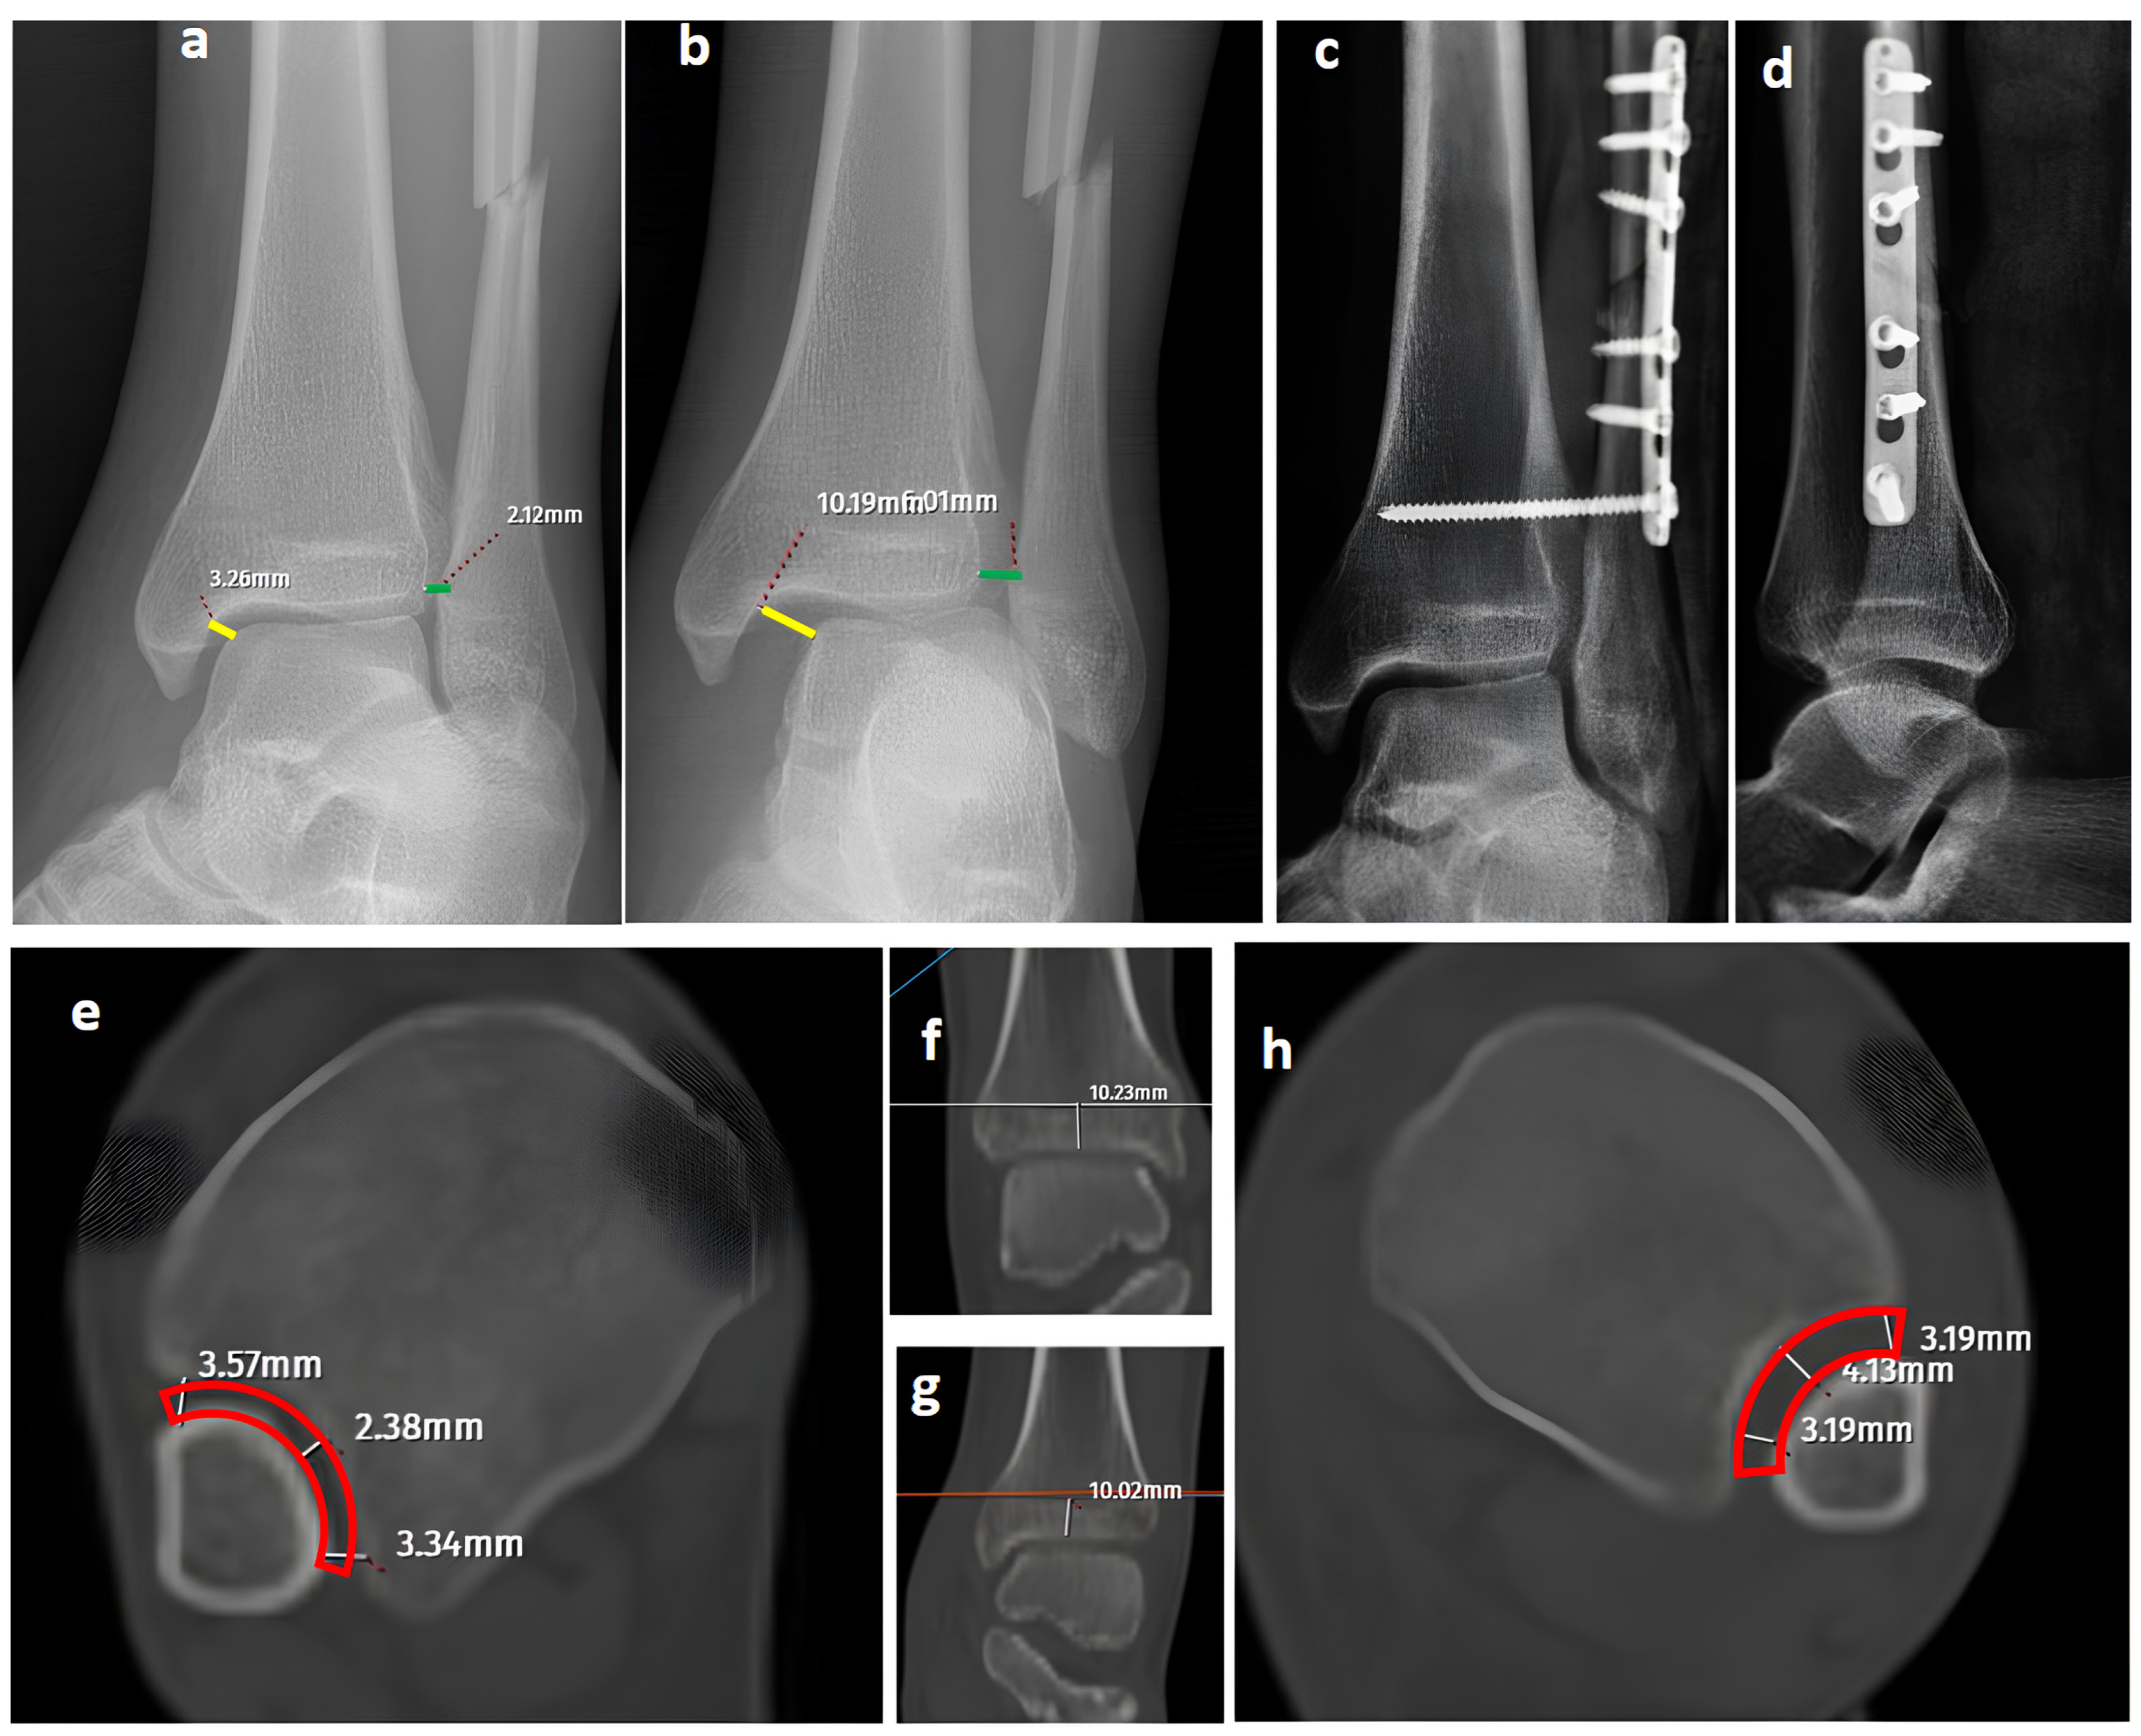

Figure 3. A bimalleolar equivalent (pronation external rotation IV) left ankle fracture. (a) A mortise view showing a high lateral malleolar fracture with normal medial clear space (yellow line) and distal tibiofibular space (green line). (b) A GAASA image showing widened medial clear space (yellow line) and widened distal tibiofibular distance (green line), indicating syndesmosis injury and deltoid ligament injury concomitantly. (c,d) Initial postoperative AP and lateral X-rays showing anatomical reduction after fixation of the lateral malleolus and syndesmosis without repair of the deltoid ligament. (eh) Axial CT images of both ankles. Although the left-side syndesmosis seems to be widened compared to the right foot, measurements are within normal ranges and do not indicate a syndesmosis injury (red block bows).

While axial CT images have provided reliable and specific assessments for syndesmosis injuries in previous studies, the diagnostic performance of CT was inferior to GAASA and mortise radiographs in this study [4]. Both inter-observer and intra-observer reliability revealed lower results compared to X-rays. This was an expected result, as the reliability of CT images is acceptable when volume measurement on axial images is performed at 10 mm over the plafond. In our study, the reason for evaluating the CT images subjectively without measurements was to mimic clinical practice scenarios where quantitative measurements are not always feasible. Relying solely on subjective evaluations of widening on axial CT images over the 10 mm plafond is potentially misleading. Even meticulous measurements on CT images do not guarantee accurate efficacy in detecting syndesmosis injuries. Yeung et al. [4] reported excellent inter-observer reliability for CT images in evaluating syndesmosis injuries. However, they found only a 56.4% sensitivity and 91.7% specificity on ROC curves, indicating the limitations of this approach. Despite excellent inter-observer reliability, the syndesmosis itself may not appear widened if unstressed or if any structures block the fibula from reducing to its proper position in CT imaging. When in a reduced position, the tibiofibular distance could appear within normal ranges on CT images and mortise radiographs (Figure 3) [1]. Researchers have proposed using direct arthroscopic visualization of the syndesmotic joint as a more precise diagnostic approach, as no imaging modality is perfect at detecting syndesmosis injuries [33]. From this perspective, some authors have utilized both conventional and dynamic ankle CT scans performed under forced external rotation, dorsiflexion, and axial loading in various foot positions. Their results revealed that applying stress significantly improves the diagnostic performance for detecting subtle syndesmotic instability [20,21]. To reduce radiation exposure and minimize the pain caused by stress applied to the ankle, ultrasonography (USG) has been utilized for the detection of ankle ligament injuries. It has been shown that ultrasound has good to excellent diagnostic value for complete discontinuity of the anterior talofibular ligament (ATFL) and the anterior inferior tibiofibular ligament (AITFL). Compared with static ultrasound, dynamic ultrasound demonstrated inferior diagnostic value for detecting complete discontinuity of the AITFL [34]. Although USG has high sensitivity and specificity in identifying ligamentous injuries such as the ATFL and AITFL, its role in assessing syndesmosis stability remains unclear. This is because the syndesmosis complex comprises five anatomical components, and in most cases, instability occurs only when all five structures are disrupted [31,35]. Furthermore, from an orthopedic surgeon’s perspective, the use of USG may not always be feasible or practical due to its operator-dependent nature, limited availability in some clinical settings, and the requirement for significant expertise to ensure accurate and reliable results.